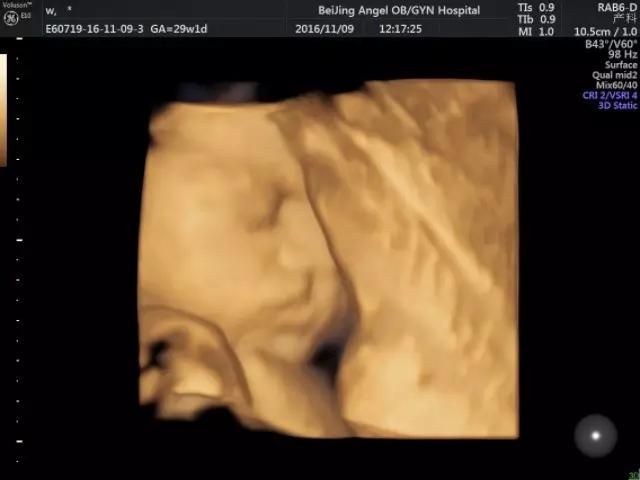

安琪E10四维彩超筛出胎儿唇裂案例

安琪E10四维彩超下宝宝萌态

四维彩超是目前世界上先进的彩色超声设备。四维彩超能够表面成像,可以更佳清晰的查出来胎儿的四肢发育是否畸形,脑膜膨出,是否唇腭裂、脊柱裂等先天畸形,及早发现及早的做出解决方案。

四维彩超可自动为胎儿进行“深宫”照相及生成动态图像,让准爸妈能清新一睹宝宝“宫”内举动和乖巧秀容,安琪超声科还可让家属陪同观看,尽享温情的亲子时光。